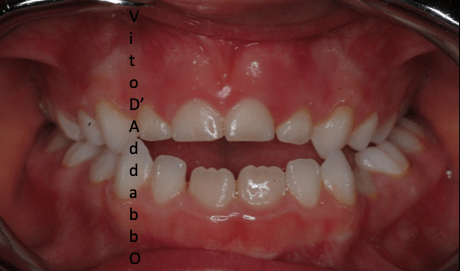

In alcune malocclusioni i denti superiori non coprono adeguatamente quelli inferiori con la presenza in alcuni casi di una beanza fra le due arcate. Questo può essere dovuto ad abitudini viziate come il succhiamento del dito, una deglutizione scorretta, una postura della lingua alterata o un problema scheletrico. In questo esempio il problema è associato ad una terza classe scheletrica.

dopo – fase 1